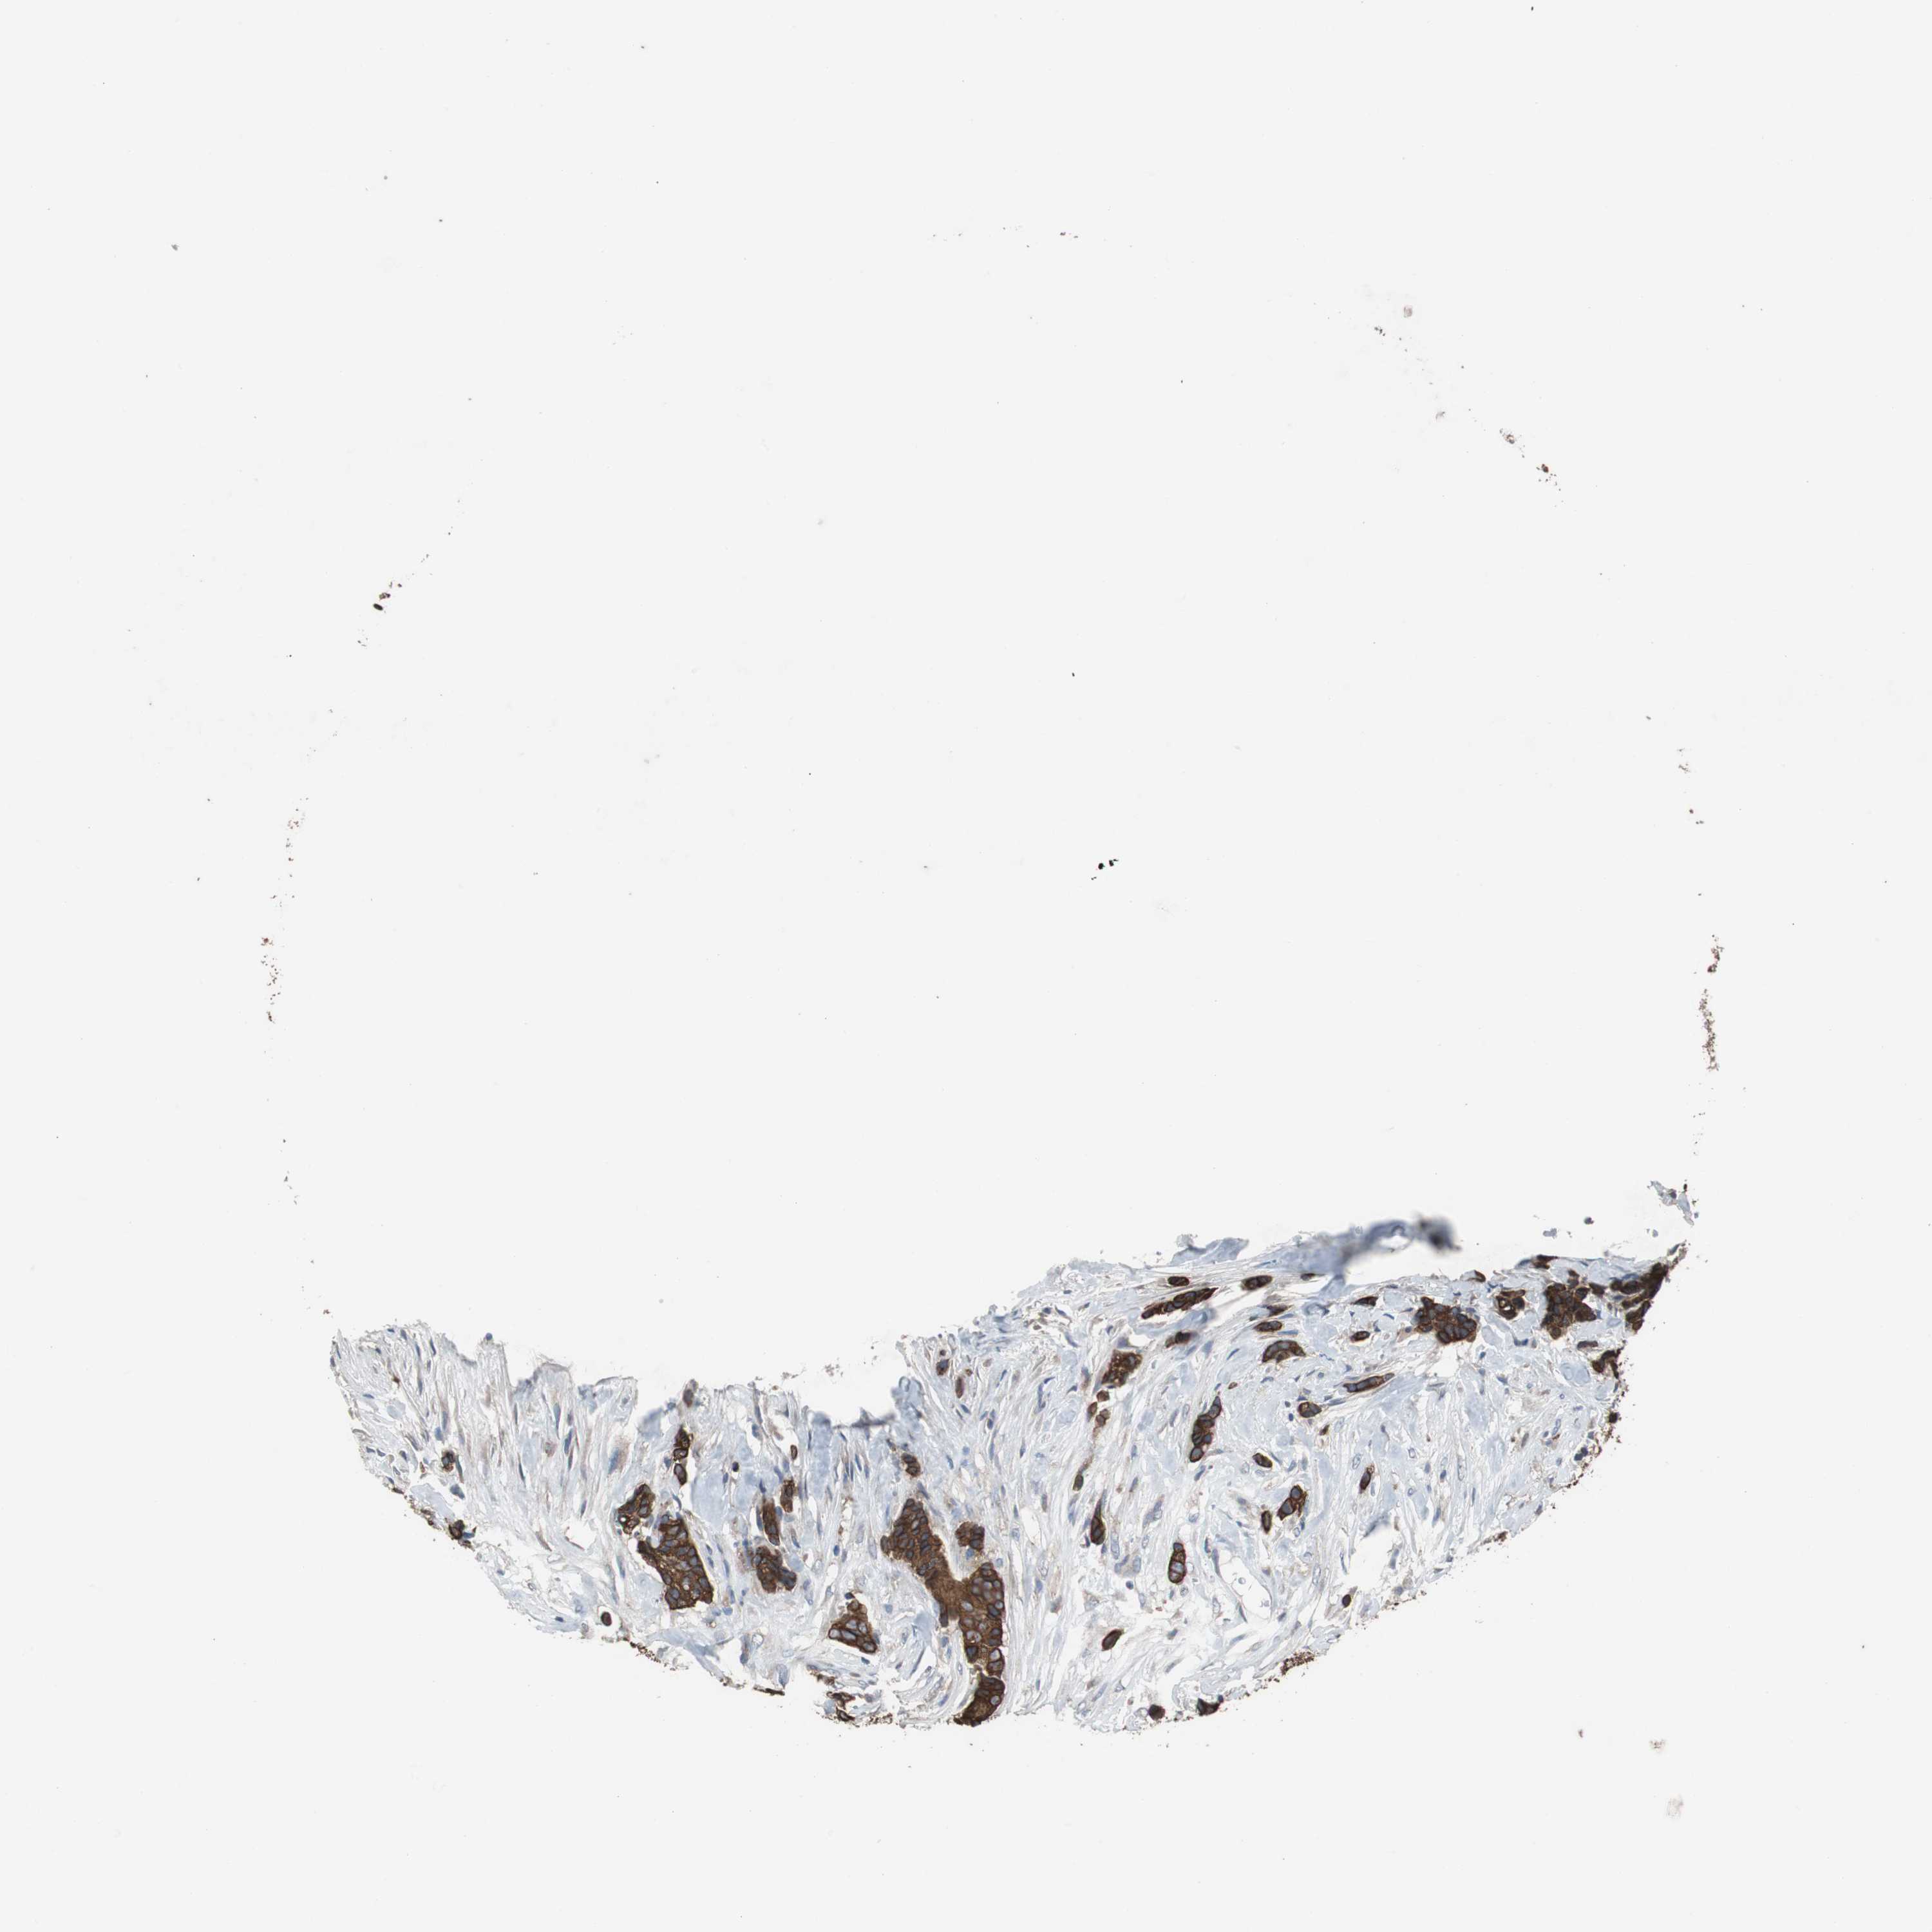

CANCER BREAST CANCER Show tissue menu

BRCA TCGA BRCA VALIDATION PROTEIN EXPRESSION